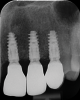

A systemically healthy 40-year-old male patient presented with a maxillary anterior vertical defect (Figure 1 and Figure 2). The patient stated that a previous bone grafting procedure was attempted in this area, but failed. The treatment plan involved a staged guided bone regeneration, the placement of three dental implants 9 months after bone augmentation, and soft-tissue grafting prior to implant loading to augment peri-implant soft-tissue thickness and keratinized mucosa width.

Fig 2. Buccal clinical view at baseline.

Figure 2

Fig 17. Final radiographic outcome at 12 months post–iCTG augmentation.

Figure 17